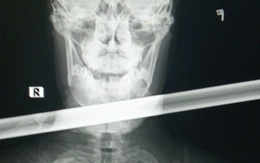

Cứu nam thanh niên bị thanh sắt dài 1,2m đâm xuyên qua vùng cằm cổ

Một thanh niên tại Quảng Bình vừa bị thanh sắt dài 1,2m đâm xuyên ngang qua vùng giữa cằm và cổ. Rất may người này đã được cấp cứu kịp thời.